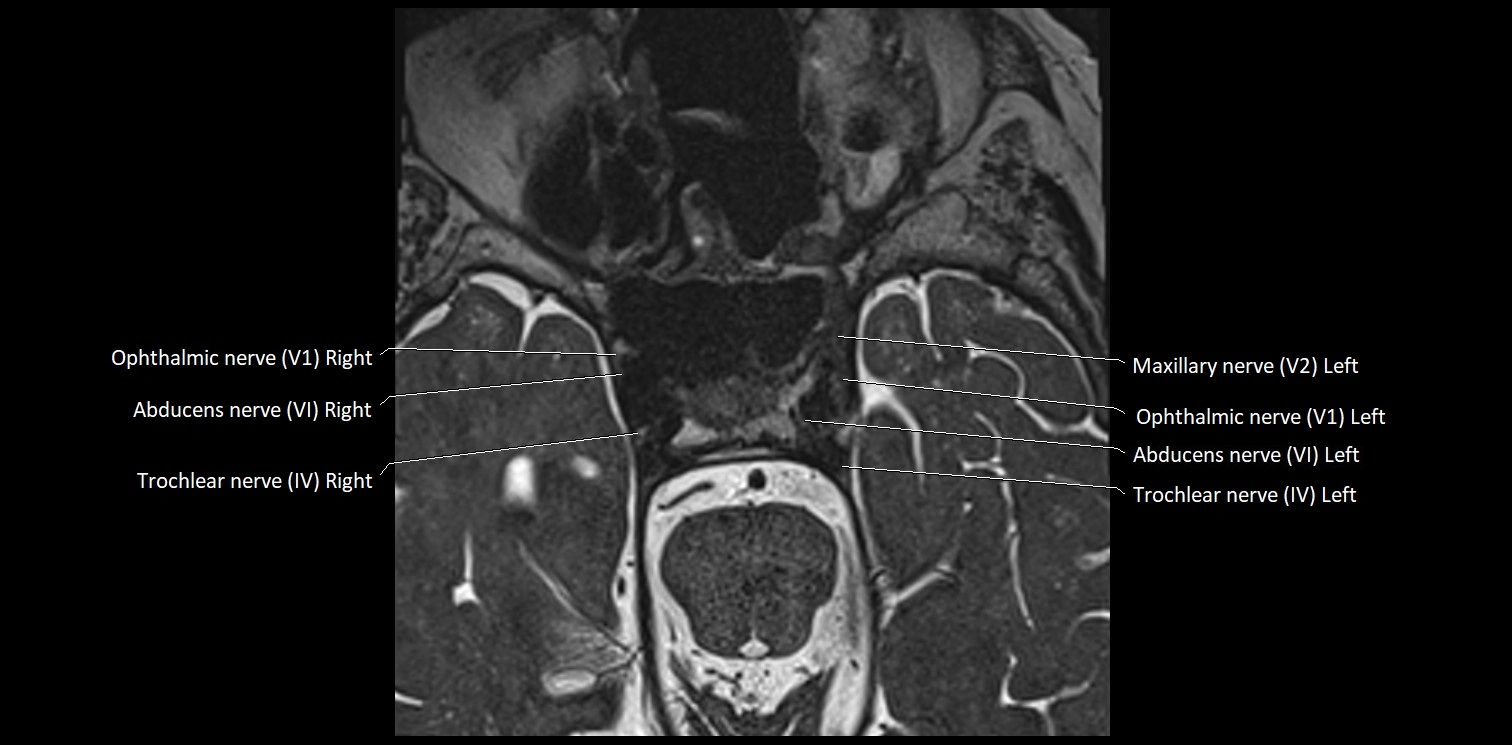

MRI Appearance

• The abducens nerve is a small, thin, linear structure

• Best visualized on high-resolution T2-weighted 3D MRI sequences (e.g., FIESTA or CISS)

• Seen as a hypointense (dark) line running from the brainstem at the pontomedullary junction, traversing the prepontine cistern, and entering Dorello’s canal under the petrosphenoidal ligament, then into the cavernous sinus, and finally the orbit

• May be challenging to visualize in standard MRI due to its small size

• Pathology may be inferred by absence, displacement, or enhancement of the nerve

MRI images

image